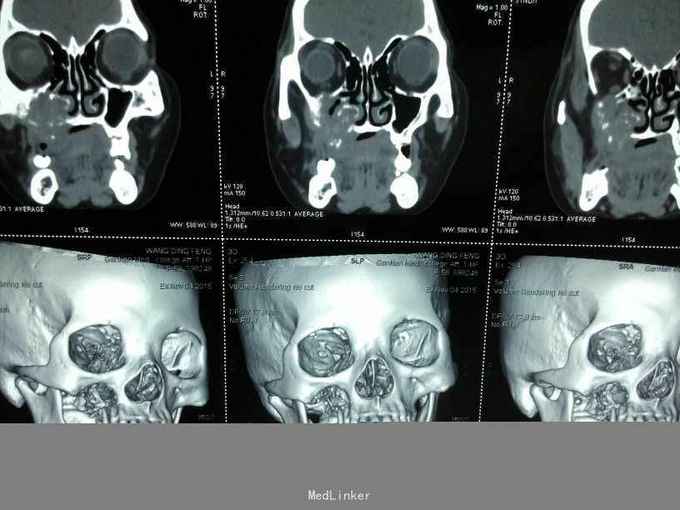

患者女,58岁,因“右上颌后区牙龈溃烂1月”入院 患者于2月前感右上颌后区麻木不适感,一月前在当地医院检查发现上颌后区牙龈溃烂,行抗炎治疗无好转。就诊于我院门诊后行病理检查提示:磷状细胞癌。

查体:心肺腹无明显异常。 专科:右上颌区颊颚侧龈、牙槽脊表面溃烂,凹凸不平,呈不规则溃疡,边缘欠佳。 辅查:CT+三围重建等,见图!

诊断:右上后牙区牙龈磷状细胞癌 治疗:右上后牙区牙龈磷状细胞癌病灶扩大切除+右上颌骨全切+右肩胛舌骨肌上淋巴结清扫术